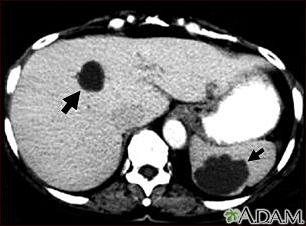

Liver and spleen cysts - CT scanBackLiver and spleen cysts - CT scanThis abdominal CT scan shows multiple cysts in the liver and spleen. Note the dark circular cyst in the liver (left side of screen) and the large, irregular, circular cyst in the spleen (bottom, right side of screen). E-mail FormEmail ResultsName:Email address:Recipients Name:Recipients address:Message: